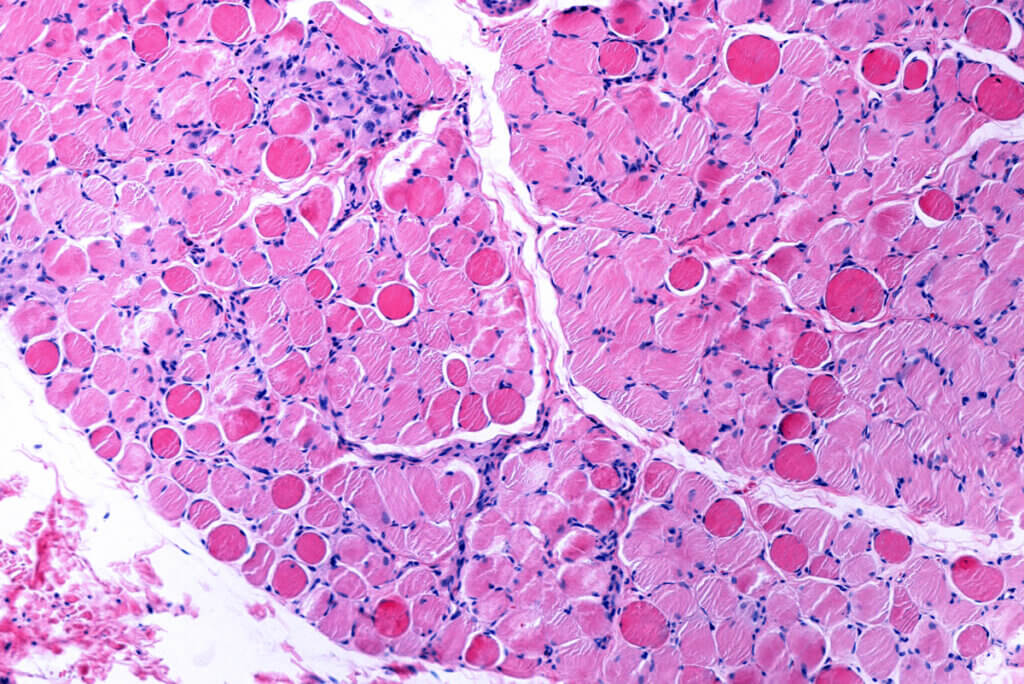

Los aminoácidos esenciales son aquellos que el cuerpo humano no puede fabricar por sí mismo. Por este motivo, han de ser introducidos por medio de la pauta dietética de forma diaria. De lo contrario, el tejido magro y muscular podrían ponerse en peligro.

Según la ciencia, se trata de una de las sustancias más influyentes en lo que a salud muscular se refiere. Participa en la reconstrucción del tejido e incrementa su funcionalidad.

No solo es capaz de influir en el rendimiento deportivo, sino que la leucina también puede reducir el riesgo de desarrollar patologías que cursen con la pérdida progresiva de la masa magra. Un ejemplo sería el caso de la sarcopenia. De hecho, la suplementación con el aminoácido podría ser un tratamiento eficaz en esta situación, según un estudio publicado en Nutrients.

Durante la tercera edad, incluir un contenido extra de leucina en la dieta se ha relacionado con una mejor funcionalidad muscular. Además, se genera una menor pérdida de tejido magro, lo que repercute de forma positiva.